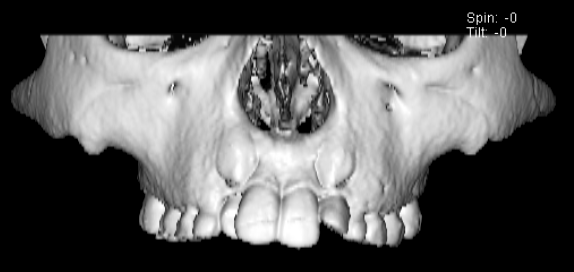

FX(フェイシャルアキシス)は85度なので東洋人の平均値に近く、下顎が前方に過剰成長するリスクは強くはありません。

しかしやはり上顎は劣成長で、下顎が優位な状態ではあります。

上下顎のギャップはありますが、顔面自体の幅径は良好な値を示していますので、スペース不足は拡大することによって解決できポテンシャルはあると考えられます。

左右の非対称もさほど強くありません。